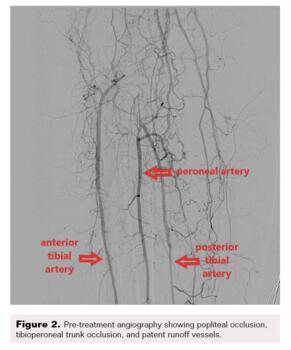

Computed tomography angiography highlighted thrombosis of the femoroposterior tibial bypass and a grade 4 Global Limb Anatomic Staging System femoropopliteal and tibioperoneal trunk chronic total occlusion (CTO). Runoff vessels were patent (Figure 2). Through retrograde posterior tibial puncture, we tried to recanalize the CTO but were not able to get into the common femoral artery (CFA) because the SFA ostium was ligated (Figure 3). We performed a short Dacron prosthetic bypass between the CFA and the proximal part of the SFA (Figure 4), followed by stenting of the whole SFA and the proximal third of the popliteal artery with drug-eluting stents. The distal part of the popliteal artery and the tibioperoneal trunk were treated with balloon angioplasty.